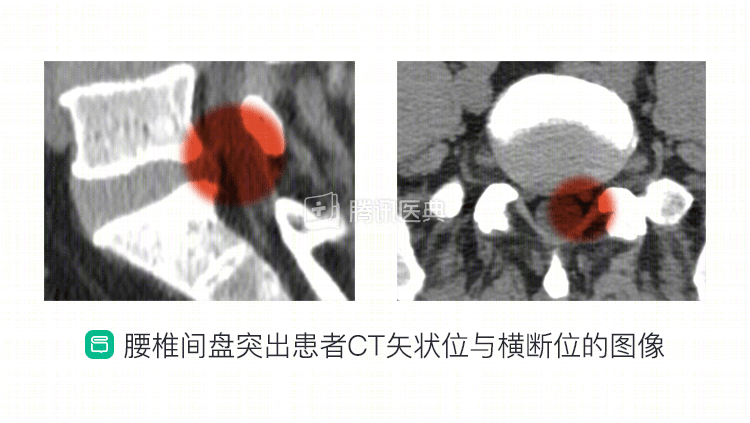

CT 图像中的腰椎间盘膨隆与突出

在诊断腰椎间盘膨隆或突出时,CT作为常规检查方法具有优势,能够清晰显示椎间盘膨隆或突出部分的大小,以及与神经根、硬膜囊的关系。同时,也可以清晰观察椎体的骨性结构、小关节和黄韧带情况。

简单来说,通过CT图像中椎间盘与椎体骨及神经根密度的差异,可以观察到椎间盘膨隆或突出以及与周围组织的关系。